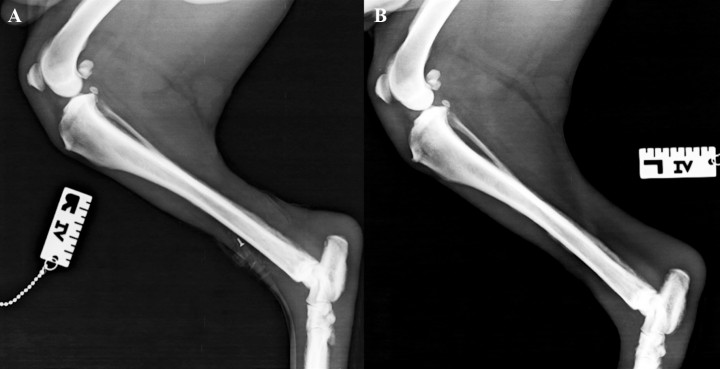

<p>Proyección mediolateral de tibia y peroné. <strong>(A) </strong>Derecha. <strong>(B) </strong>Izquierda.</p>

Proyección mediolateral de tibia y peroné. (A) Derecha. (B) Izquierda.

<p>Mismas radiografías de la Figura 3. Se observa reacción perióstica del tipo en empalizada (ver flechas) en el aspecto dorsal del cuerpo del metatarso y del hueso calcáneo con afectación del tercio distal de la diáfisis de la tibia en su aspecto caudal. La rótula presenta en su cara craneal las mismas lesiones, al igual que el tercio distal de la diáfisis del fémur. En la extremidad posterior izquierda se observa afectación del hueso calcáneo, del tercio distal de la diáfisis de la tibia en su aspecto caudal y en el aspecto craneal del fémur. No existe afectación de las superficies articulares. Tumefacción de los tejidos blandos del tarso.</p>

Mismas radiografías de la Figura 3. Se observa reacción perióstica del tipo en empalizada (ver flechas) en el aspecto dorsal del cuerpo del metatarso y del hueso calcáneo con afectación del tercio distal de la diáfisis de la tibia en su aspecto caudal. La rótula presenta en su cara craneal las mismas lesiones, al igual que el tercio distal de la diáfisis del fémur. En la extremidad posterior izquierda se observa afectación del hueso calcáneo, del tercio distal de la diáfisis de la tibia en su aspecto caudal y en el aspecto craneal del fémur. No existe afectación de las superficies articulares. Tumefacción de los tejidos blandos del tarso.